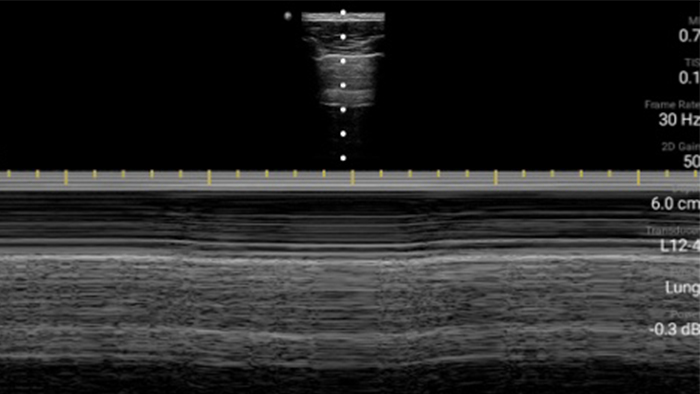

Utilice Lumify para la evaluación de las vías respiratorias y pulmonares

Las soluciones Lumify POCUS pueden ayudarle a detectar el tubo endotraqueal dentro de la tráquea, ayudar en los procedimientos de cricotirotomía emergentes, en el diagnóstico de derrame pleural y enfermedades alveolares intersticiales.